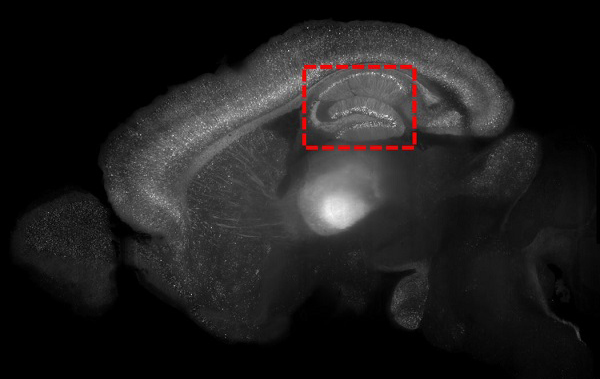

July 5, 2018

Our earliest memories may be forgotten but not lost

A new study from SickKids shows that early memories in mice are not missing and can be brought back by directly stimulating different clusters of neurons that represent individual infantile memories in the brain.